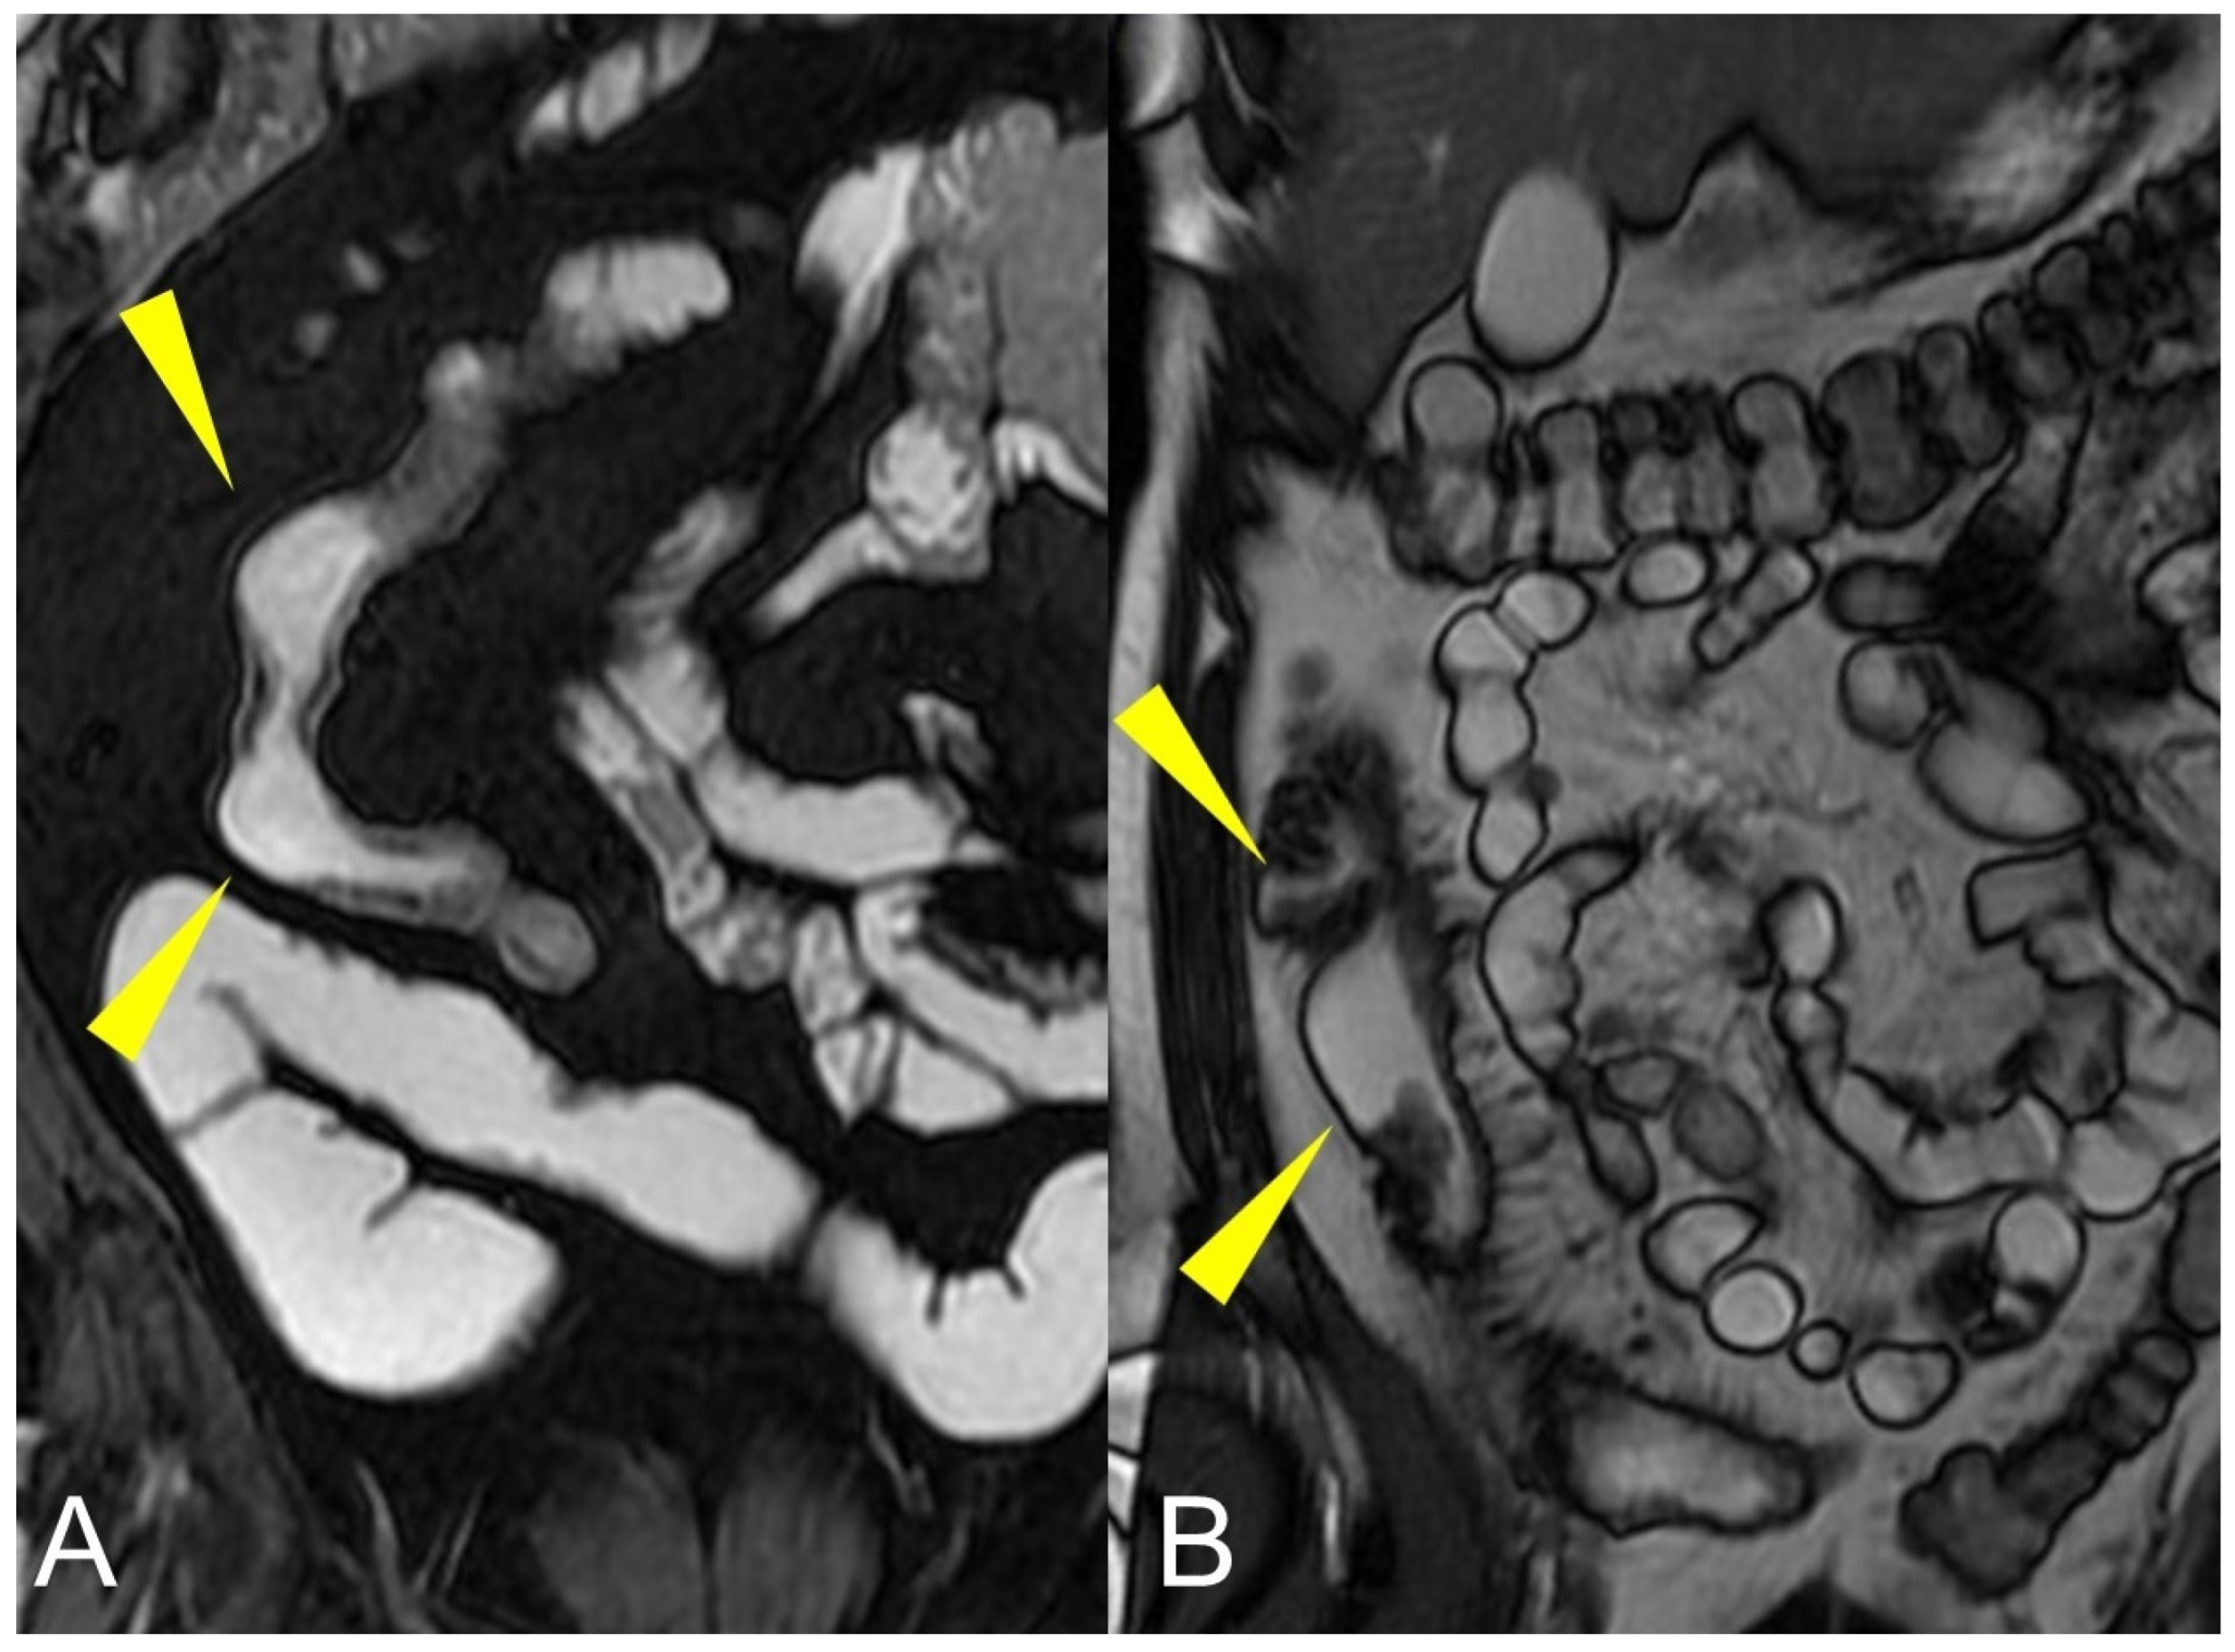

Bruining et al. [6] well described this known and anecdotal crucial point reporting the differences between a long and a short rigid stenosis in terms of therapeutic approach and clinical relevance. In fact, relative moderate bowel stenosis distributed over a long segment behaves as a short but pre-occlusive stenosis, preventing intestinal flow and resulting in the upstream dilation of the normal loops. This is defined as a functional stenosis that will probably lead to bowel obstruction whereby a conservative non-surgical treatment would be fallacious. Therefore, it is necessary to know the location of the pathological tissue influencing the medical or surgical therapeutic choices [6] (Figure 1 and Figure 2).

Figure 1.

Quantification of intestinal strictures. Coronal fast imaging employing steady-state acquisition (FIESTA) images (A–F) show a long segment of the distal ileum affected by pathology (yellow arrowheads) showing, reduction in caliber, stiffness, and absent peristalsis. The upstream loops are extremely dilated (green arrowheads) indicating that, although a tight stenosis of the lumen is not appreciable, the long segment reduced in caliber behaves as if it were a pre-occlusive stenosis, preventing the transit of intestinal contents with massive dilatation of the upstream loops. This condition represents a functional stenosis that needs to be treated surgically to prevent repeated subocclusions or intestinal obstruction or other complications.

Figure 2.

Quantification of intestinal strictures. Coronal fast imaging employing steady-state acquisition (FIESTA) images (A,B) show a long segment of the distal ileum affected by pathology (yellow arrowheads). The upstream loops do not show dilatation (green arrowheads) because the pathological loops do not show significant abnormal stiffness or massive luminal reduction. This condition represents a no-functional “stenosis” because the intestinal flow is preserved, so there is no risk of sub-occlusions or intestinal obstruction.